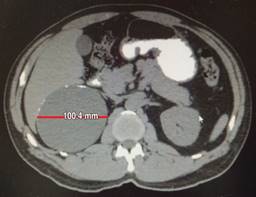

Biometría hemática, pruebas de función hepática, renales, TP y TPT de mayo de 2018 normales. No se realiza cortisol, aldosterona, catecolaminas urinarias ni metanefrinas. Tomografía de mayo reporta en glándula suprarrenal derecha imagen hipodensa con diámetros máximos de 101 mm, calcificaciones en su interior con efecto ocupativo y compresivo sobre las estructuras vecinas (Figuras 3 a 6). Completándose su valoración preoperatoria por medicina interna, se programa abordaje quirúrgico anterior abierto y bajo profilaxis antibiótica con ceftriaxona 2 g en dosis única, se realiza incisión subcostal derecha, destechamiento con electrocauterio de quiste suprarrenal derecho de 10 × 9 cm, con adherencias al hígado, contenido de aproximadamente 400 ml de líquido hialino y calcificaciones de alrededor de 20 × 40 mm en su interior. Se coloca drenaje abierto, penrose de ½” (19 mm) en espacio subfrénico ante la sospecha de hemorragia postoperatoria.